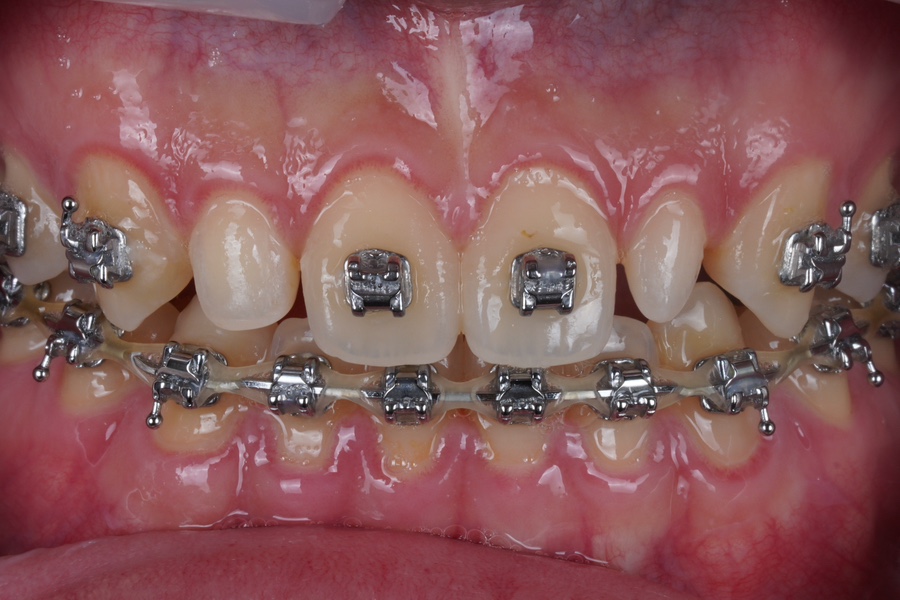

왜소치만 교정기 뗀 사진

교정기를 왜소치 부분만 떼고

철사를 뺀 상태에서 오셨습니다.

이렇게 와주시면 참 좋아요.

아니면 교정기 다 떼고

유지장치 부착 전에 오시는 게 BEST입니다.

교정기를 떼니까 왜소치가 눈에 띄죠?

왜소치는 아무래도

교정만으로는 치료가 어렵기때문에

아까 말씀드린

라미네이트나 크라운 치료를 보통 권하는데

우리 재주좋은치과에서는

완.전. 무삭제

레진비니어로도 치료가 가능합니다.